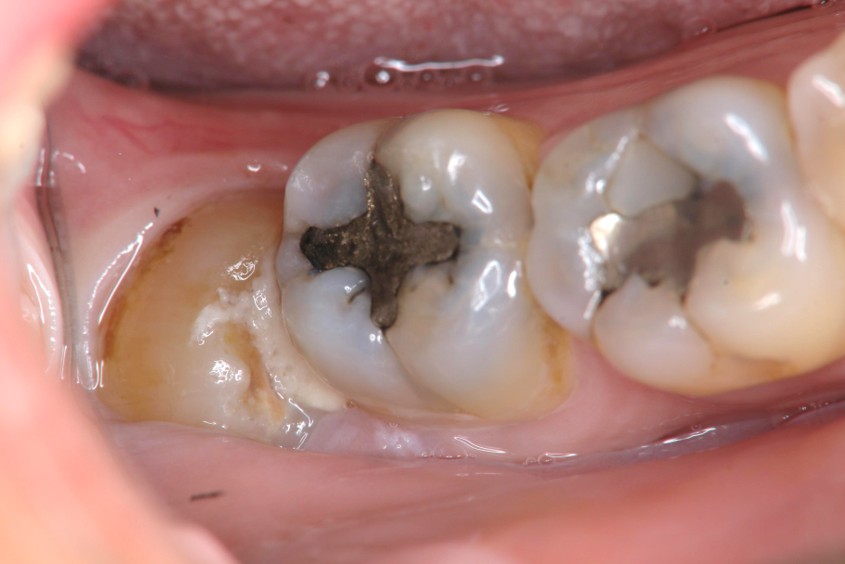

治療前,右下阻生齒造成牙周腫脹